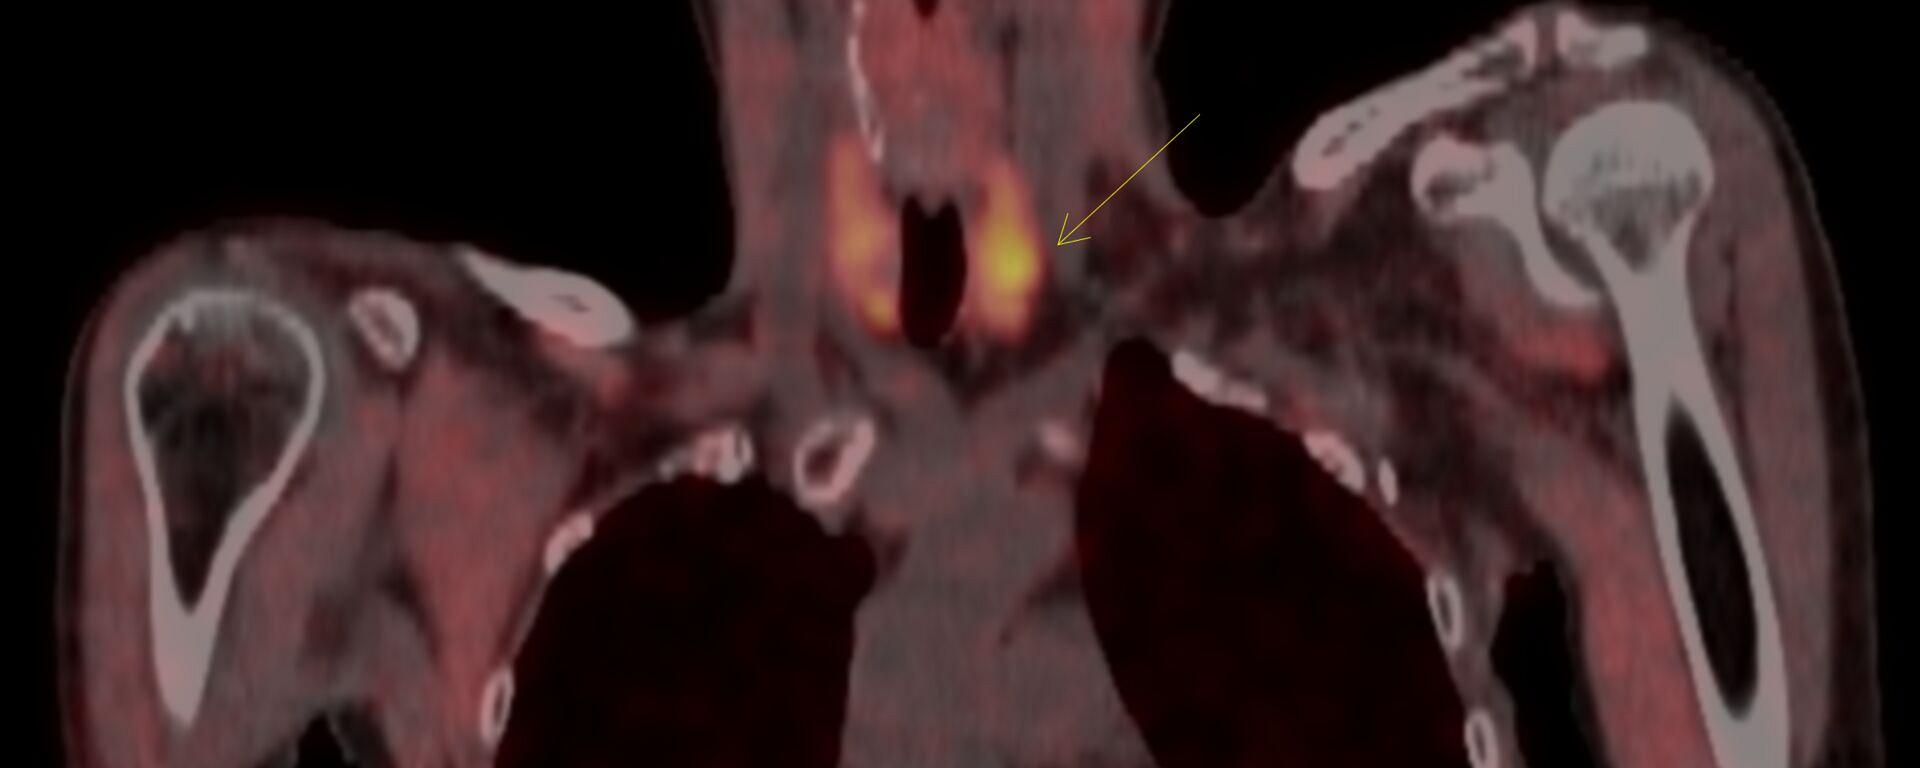

Beeldvormend onderzoek is belangrijk voor het identificeren van hyperfunctionele bijschildklieren bij patiënten met primaire hyperparathyreoïdie (pHPT). De diagnose pHPT wordt allereerst gesteld op grond van biochemische bepalingen van het bijschildklierhormoon en de calciumspiegels in serum. Vervolgens is beeldvorming noodzakelijk om een oorzakelijk bijschildklieradenoom te lokaliseren. Eerstelijns beeldvormingstechnieken zijn op dit moment 99mTechnetium(Tc)-sestamibi-bijschildklierscintigrafie met SPECT/CT, al dan niet gecombineerd met hoge-resolutie halsechografie met kleurendoppler. In de tweede lijn is er een plaats voor 18F-gelabelde cholinederivaten met PET/CT, 4-dimensionale CT, waarbij blanco, arteriële, veneuze en late fasen worden afgebeeld, en MRI. Parathyreoïdectomie is de enige curatieve behandeling voor pHPT. In ervaren handen wordt het succes van minimaal invasieve parathyreoïdectomie mede bepaald door een nauwkeurige pre-operatieve lokalisatie van één of meerdere hyperfunctionele bijschildklieradenomen.